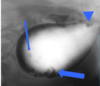

What are these and what is the significance?

Renal coritcal cysts

Fluid filed cavities.

You will see one or two cysts in the cortex! Often incidental. If you have many cysts e.g. polycystic kidney dx – reduce the amount of functional tissue = problems